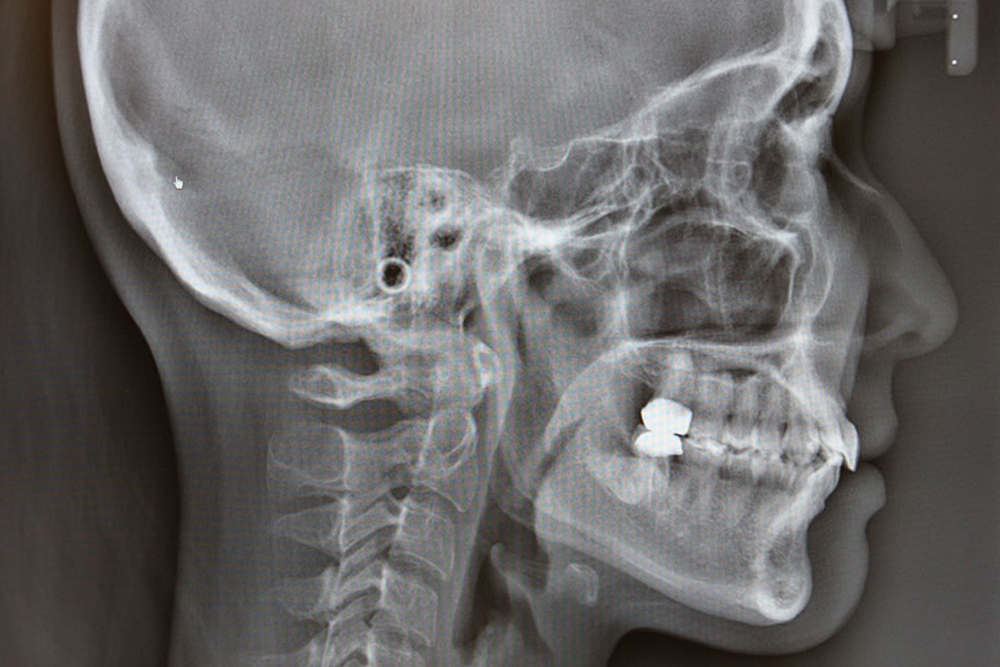

セファロレントゲン

頭部から顎までのX線画像が撮影できます。矯正治療の診断、治療経過の確認の際に使用します。